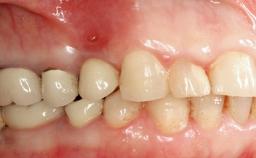

Peri-implant Carcinoma

Maximilian Moergel, Peer Wolfgang Kämmerer, Bilal Al-Nawas

Oral implants are highly successful and offer long-term benefits, especially in the rehabilitation of edentulous patients or patients with oral defects following ablative tumor surgery (Albrektsson and coworkers 1986), and also after radiation therapy (Schiegnitz and coworkers 2014). With the number of implants placed globally going into the millions, implant dentists have observed some rare adverse events. Although carcinogenesis around implants is an exceedingly rare phenomenon, we recently reported about 15 patients treated for carcinomas adjacent to implants at our clinical department over a period of fifteen years (Moergel and coworkers 2014). The following case represents a patient of this cohort; it discusses possible risk factors and makes suggestions for a recall schedule. A 70-year-old woman was referred to our outpatient department for evaluation of a rapidly growing macroscopic alteration of the mucosa in the left mandible.